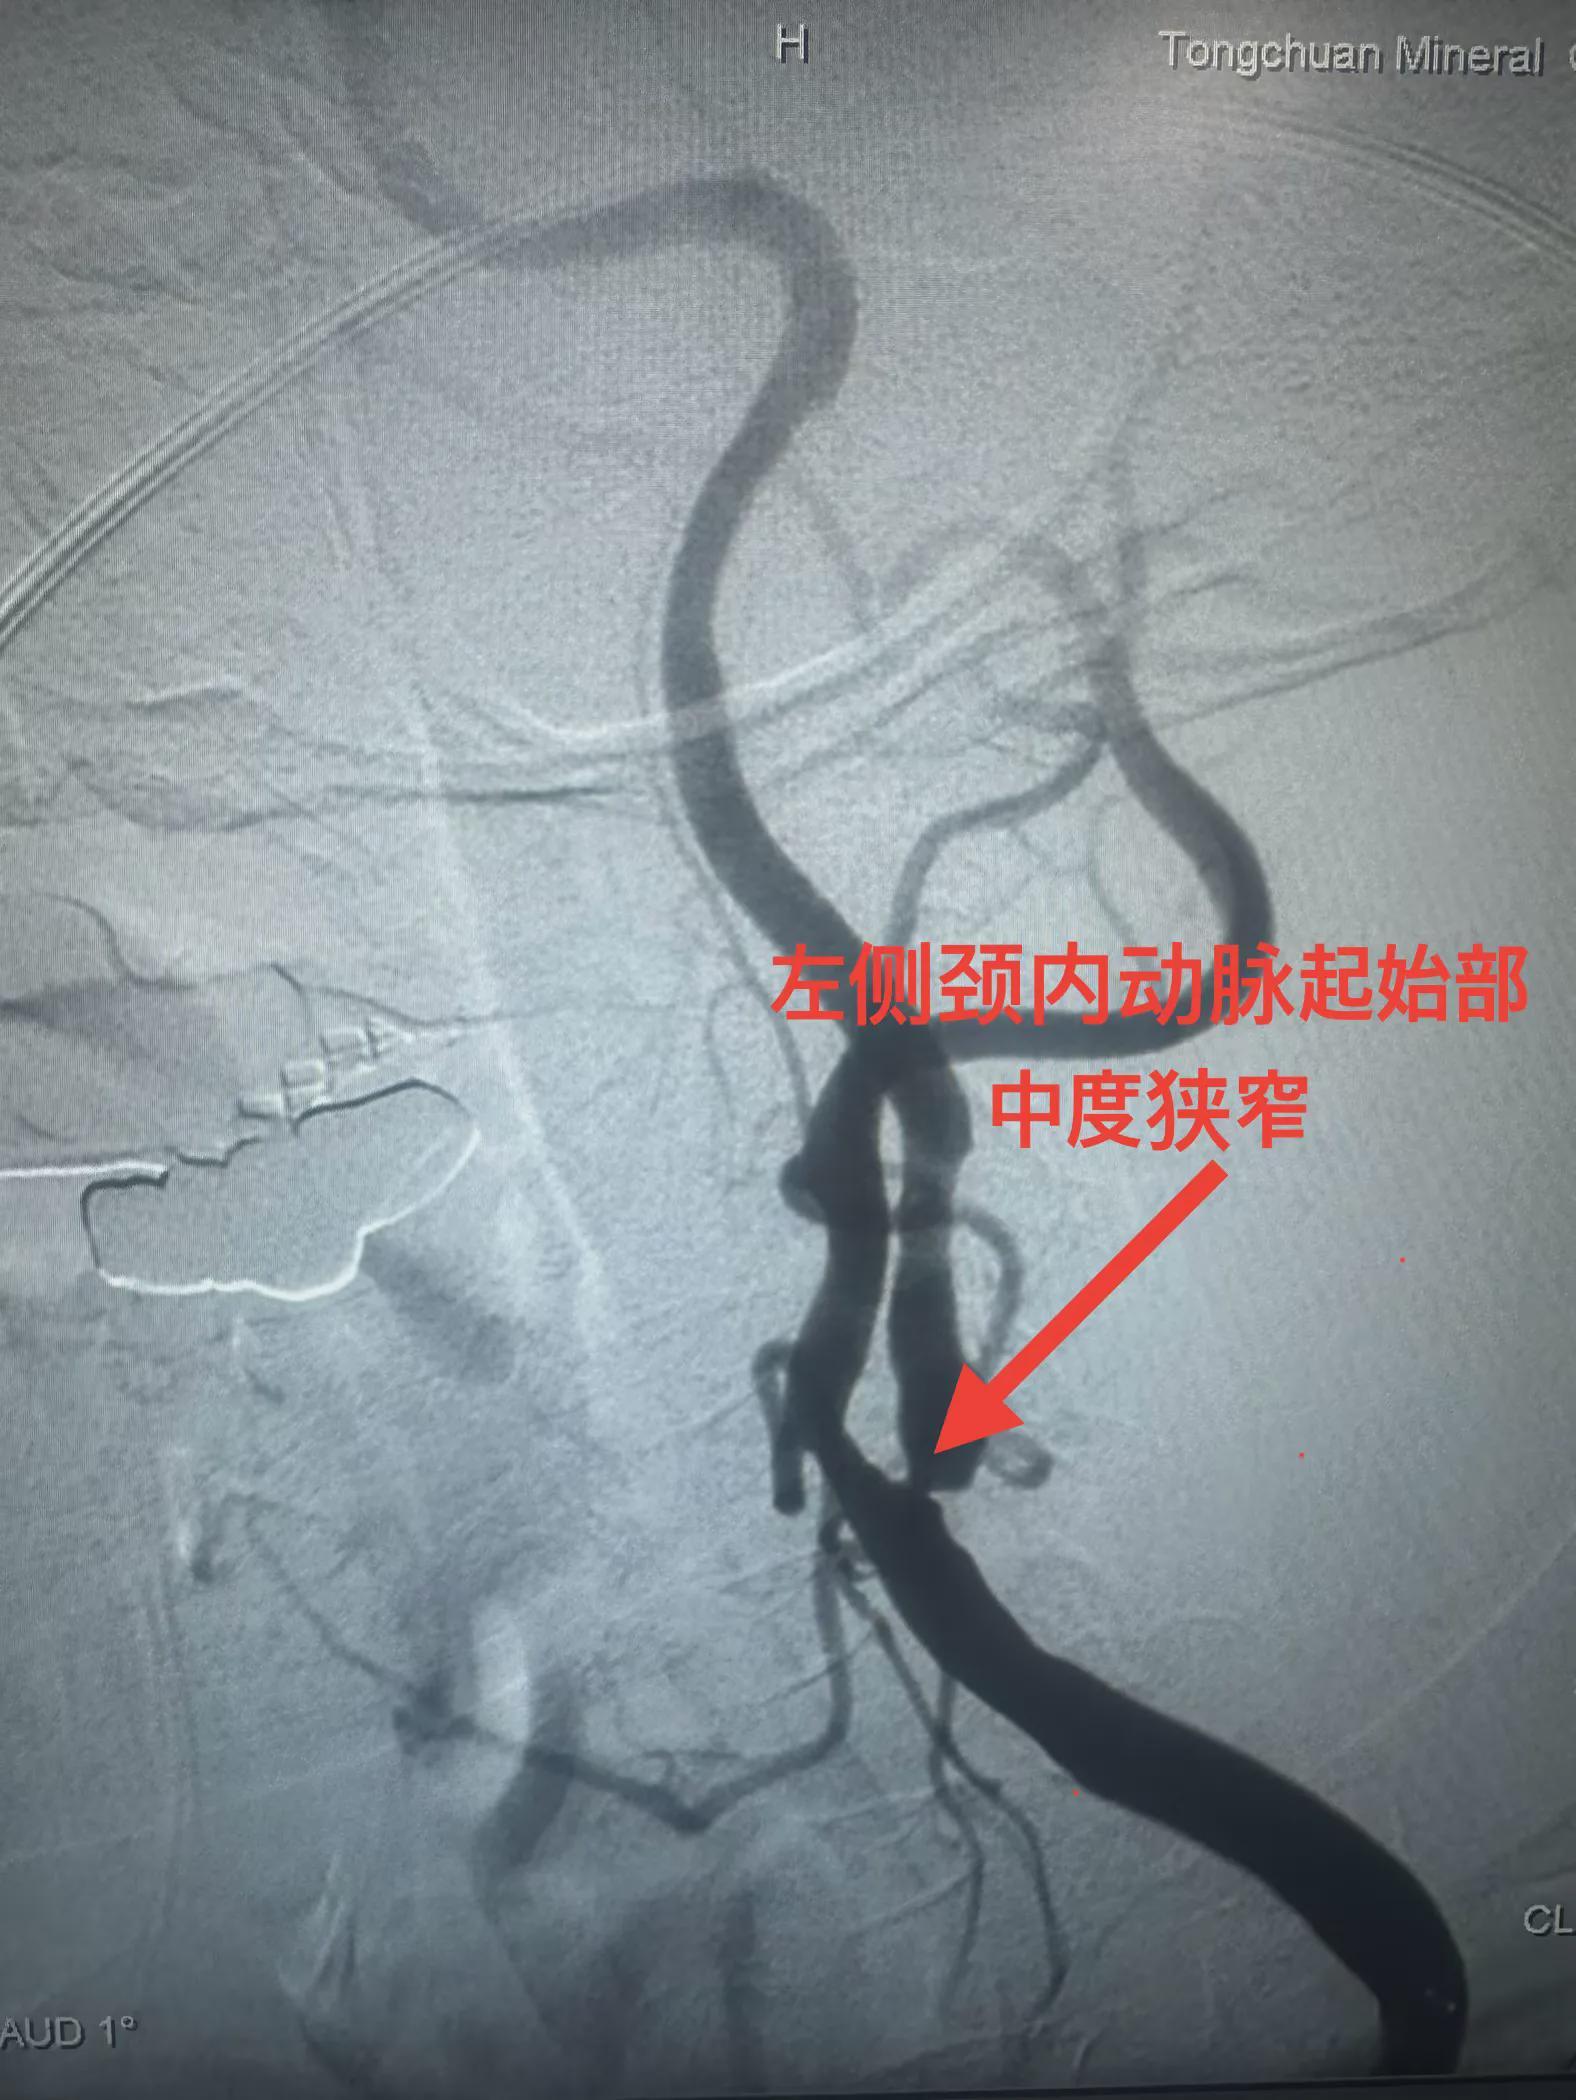

患者系77岁女性,因发作性言语不清、右侧肢体无力6小时入院。入院后,行核磁共振检查提示多发性陈旧脑梗,并进一步行全脑血管造影,显示左侧颈内动脉起始部中度狭窄。考虑到患者病情特点,铜川矿务局脑血管首席专家兼卒中中心名誉主任李健教授和学科带头人邵元主任决定带领团队采用OCT技术进行辅助支架植入治疗。

神经内二科团队为患者行球囊扩张手术后,经导引导管将超声诊断导管送至狭窄处远端,连接专用超声诊断仪器后进行了血管腔内超声扫描,清楚显示球囊扩张后血管形态,及血管内膜与斑块破损情况,并在超声诊断基础上,根据血管形态判断,准确置入支架,精准解除了血管狭窄,让患者获得了更为精确的治疗。